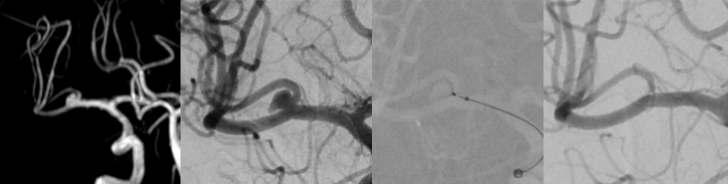

Neuroradiology is your contact partner for diagnostics and minimally invasive therapy of diseases and changes of the nervous system, i.e. of the brain and spinal cord, peripheral nerves and the immediate adjacent structures (e.g. the spine).

Diagnostically and therapeutically, the most modern methods and equipment are available for our patients. In addition to diagnostic neuroradiology, our clinic is characterized by a high level of expertise in minimally invasive neuroradiological therapy, both in the emergency treatment of strokes and in the elective treatment of aneurysms, vascular stenoses and vascular malformations.